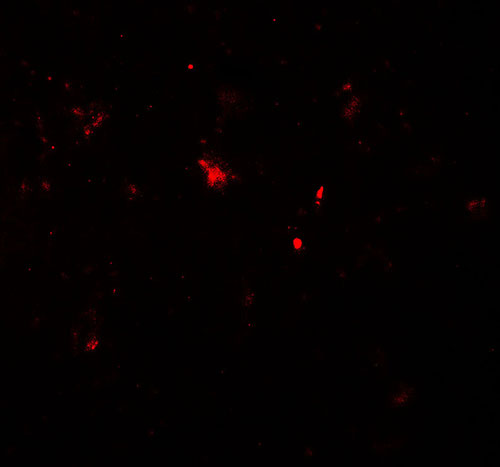

Immunofluorescence of PARK2 in human brain tissue with PARK2 antibody at 20 μg/ml. |